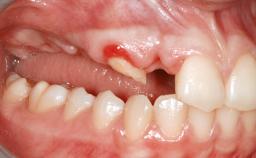

A 45-year-old woman with a completely edentulous maxilla was referred to evaluate the possibility of rehabilitation with an implant-supported prosthesis. This patient was healthy and a non-smoker. She had been wearing a maxillary complete denture opposing a natural mandibular dentition since her twenties. This situation had resulted in progressive resorption of the alveolar ridge, repeatedly creating a need for relining the denture. Twenty years later, despite multiple adaptations and the use of “glues” the denture was unstable and causing the patient psychological and functional discomfort.

Bone Augmentation Horizontal|Sinus Floor Elevation|Staged|Vertical

Soft Tissue Grafting Staged